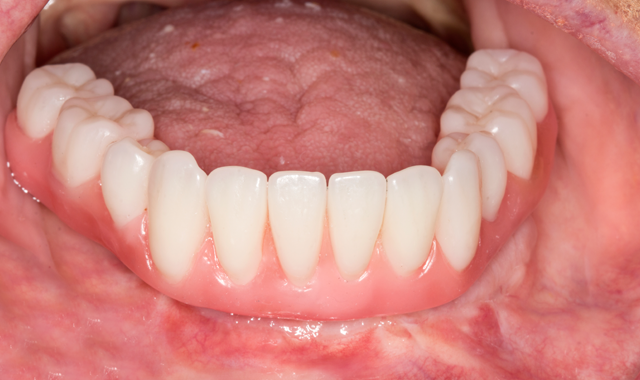

However, the fabrication is technique sensitive and should follow the appropriate clinical and laboratory steps discussed in this case study. The patient outcome showed high success in function, esthetics, phonetics and high patient satisfaction (Figs. 16-17).

Fig. 16

Figure 17